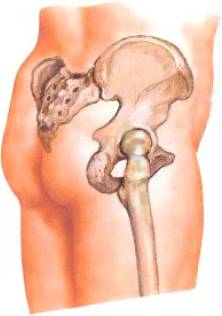

髋关节

今天的主角髋关节,俗称“胯骨轴”。它是人身体上最灵活的关节(和肩关节并列),是一个球窝关节,可以做出很多方向的运动。

就是上图中那个圆球,嵌在我们骨盆里的那个,如果你看过上一篇活儿姐之前发过的《屁股不翘、小肚子还突出,可能是你的体态出了问题》的话(关注【美丽也是技术活】,回复“翘臀”就好),你应该知道图中哪部分是骨盆。

这个髋关节是干啥用的呢?髋关节最大的作用就是负责站姿状态下力线的传导,上半身的自重在顺着脊柱一节一节向下压到骨盆后,由髋关节分导到双腿上。